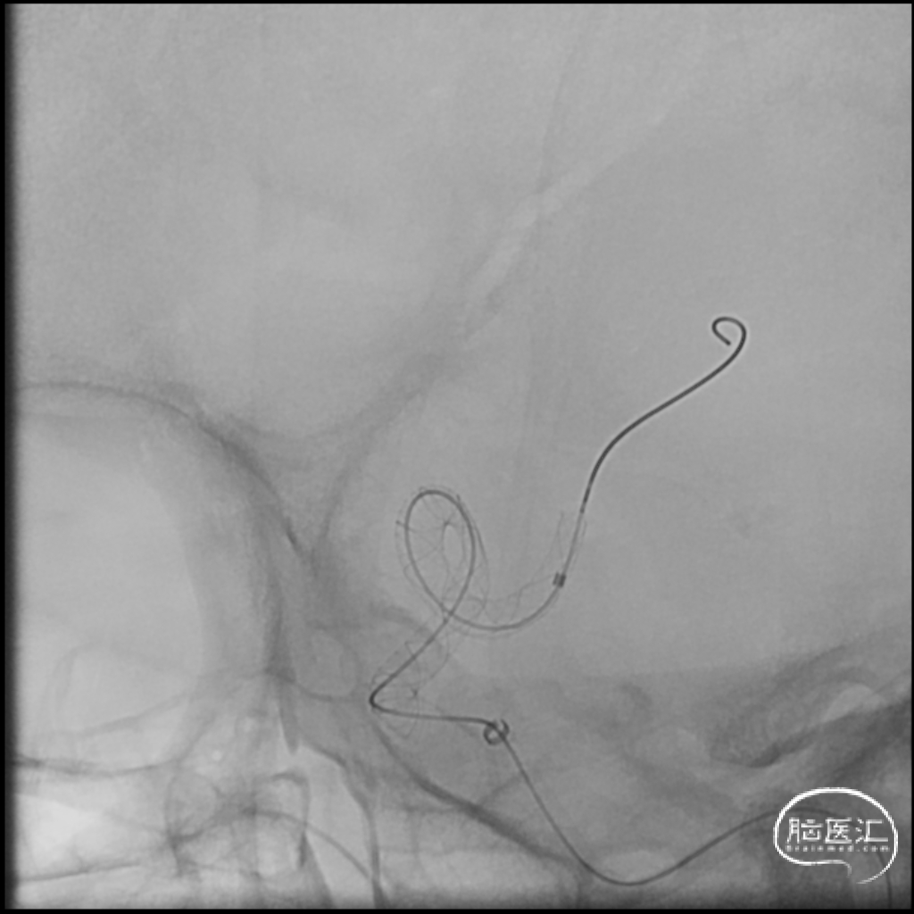

6F 90cm长鞘+6F 115cm中间导管

SL-10/synchro .014,5X速度

交换3m Floppy,Gateway 1.5mm/9mm,6atm

Pos-dilatation

Maverick 2mm/15mm,6atm

支架微导管Frepass